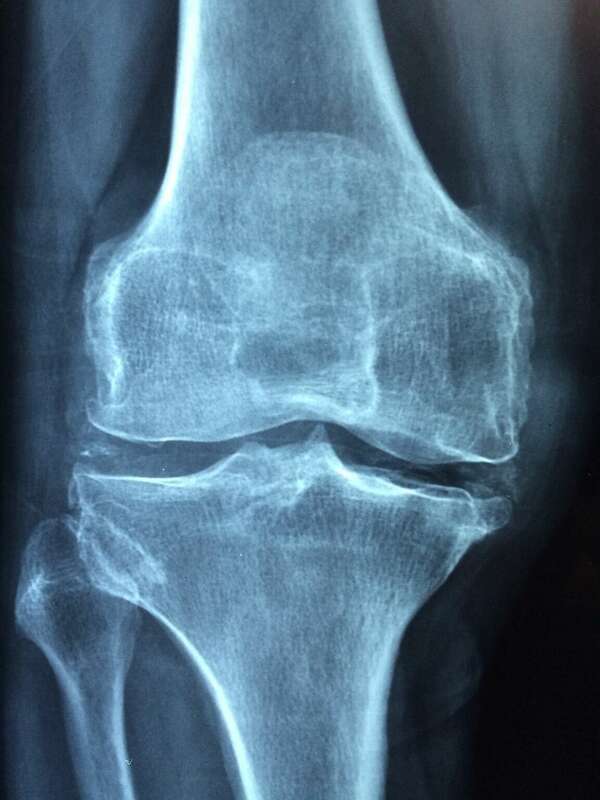

Douleur au niveau des genoux :

Définition

C’est une Ostéochondrose (maladie de croissance) qui touche le genou de l’enfant et de l’adolescent entre 10 et 15 ans. Plus particulièrement, il ...

Problème provoquant de vives douleurs au niveau du genou dans la région entre le fémur (fémoro) et la rotule ( patellaire). Syndrome assez courant...

Le ménisque joue un rôle d’amortisseur entre le fémur et le tibia dans le genou. Une lésion méniscale est une lésion de ce ménisque avec une déchi...

Le ligament Latéral Externe (LLE) est le ligament présent sur la face exterieur du genou. Sous lésion nous avons , la rupture, ou déchirure du lig...

Les ligaments croisés sont les ligaments se situant à l' et qui fixent le tibia au fémur. Ils sont au nombre de deux.

Sous lésion nous avons , la ...

définition :

Latéral Interne (LLI): Le est le ligament qui se trouve sur la face interne du genou. Sous lésion nous avons, la rupture, ou déchirure du ligament.

1. Majorité des cas: Trauma...